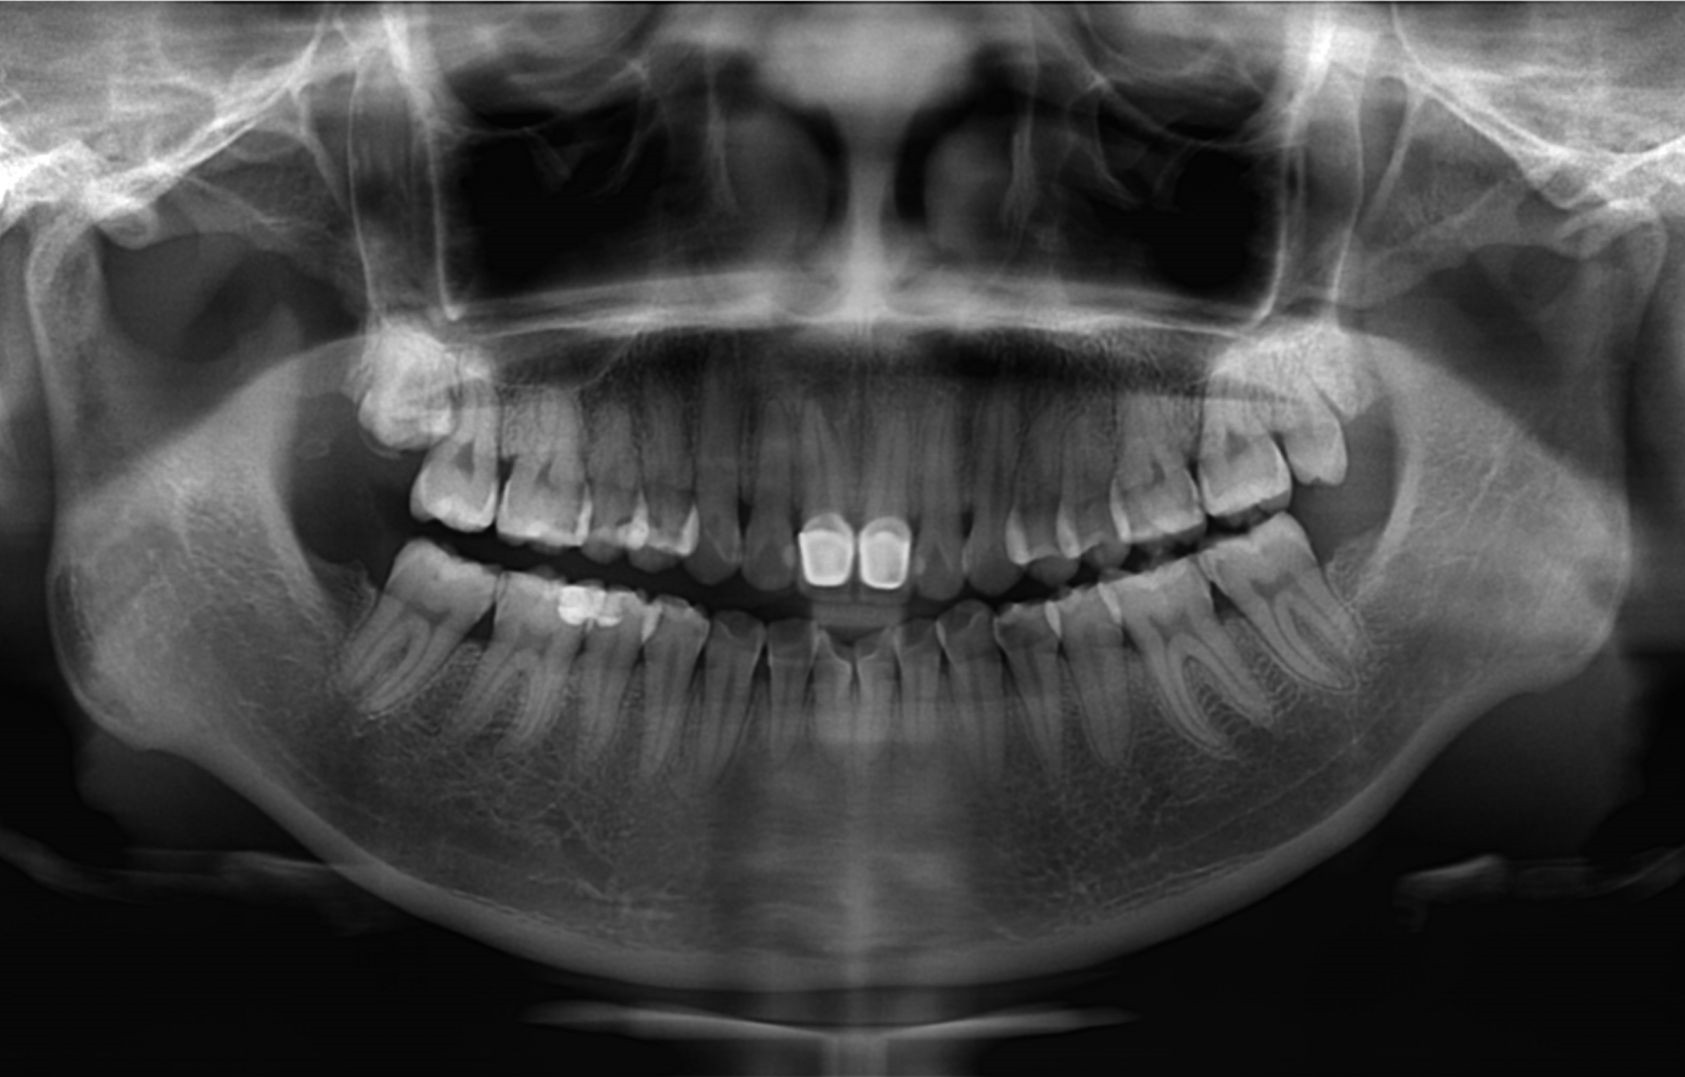

牙片分为几种?X线片一般分为全景片、根尖片、X线头影测量以及CT , 具体需要根据每个人的牙齿情况而定 。

01 全景片